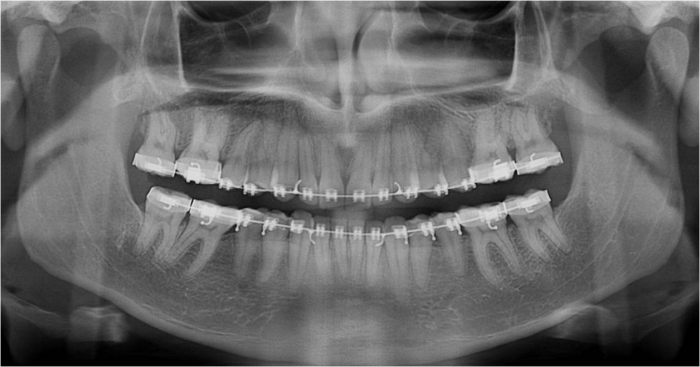

Raio X após cirurgia